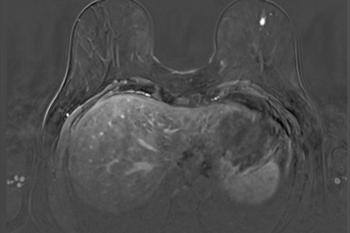

Dexamethason könnte Brustkrebs-Metastasen reduzieren

Das Medikament Dexamethason ergänzt Krebsbehandlungen, um Nebenwirkungen der Chemotherapie wie etwa Übelkeit und Entzündungen zu mildern. Forschende der Universität Basel haben nun entdeckt, dass es darüber hinaus auch Metastasen bei bestimmten Typen von Brustkrebs bekämpft.